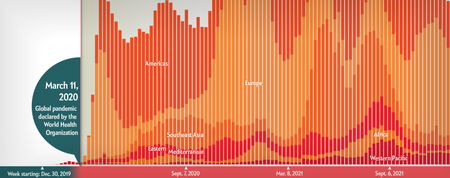

COVID’s Uneven Toll Captured in Data

Visualizing ongoing stories of loss, adaptation and inequality